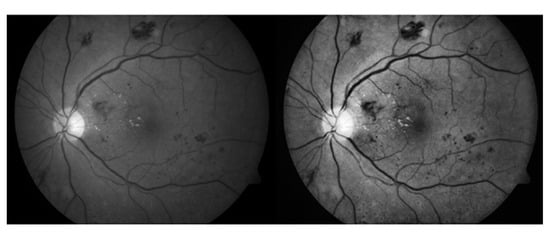

The testing dataset is classified into two classes, i.e., healthy images and DR images identified by given datasets specialist ophthalmologists, who split the 1509 images showing hemorrhages into 573 images. When the proposed method was tested on healthy images, no hemorrhages was detected. Table 2 shows a complete description of all used datasets. Figure 8 shows an example of digital retinal imaging with hemorrhages present.

Figure 8.

Example of a retinal image with hemorrhages. The color bars show the relative intensity of the image.